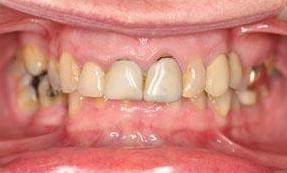

This adult patient had heavily restored discolored and defective upper front teeth. Their upper front four teeth were rejuvenated with new crowns to give the finished smile.